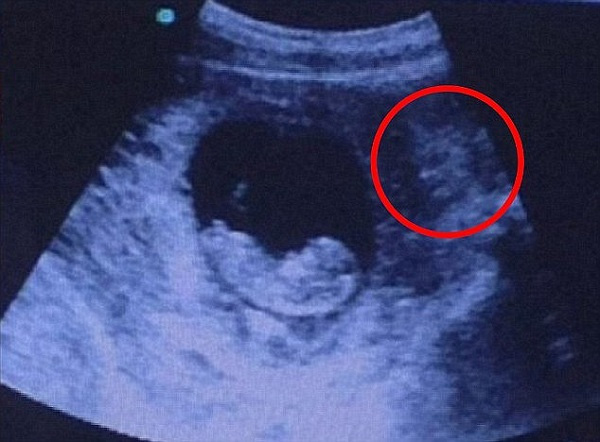

Đây không phải lần đầu tiên trong bức ảnh siêu âm thai nhi xuất hiện những hình ảnh kỳ lạ khiến người xem phải giật mình. Đã có rất nhiều hình ảnh siêu âm với các hình thù khác lạ như khuôn mặt một con quỷ dữ, khuôn mặt của vua Arthur hay thần bóng tối Darth Sidious.

Hồi đầu năm 2016, một bức ảnh xuất hiện trên imgur cũng được lan truyền nhanh chóng. Một số người cho rằng đó có thể là khuôn mặt của một nhân vật thần thoại nào đó, đa số cho rằng trông nó rất dữ tợn với đôi mắt đen và chiếc sừng trên trán. Có người lại cho rằng: “Hình ảnh bên phải giống nữ thần Hindu”, số khác lại cho rằng: “Giống một nàng tiên cá thân thiện”.